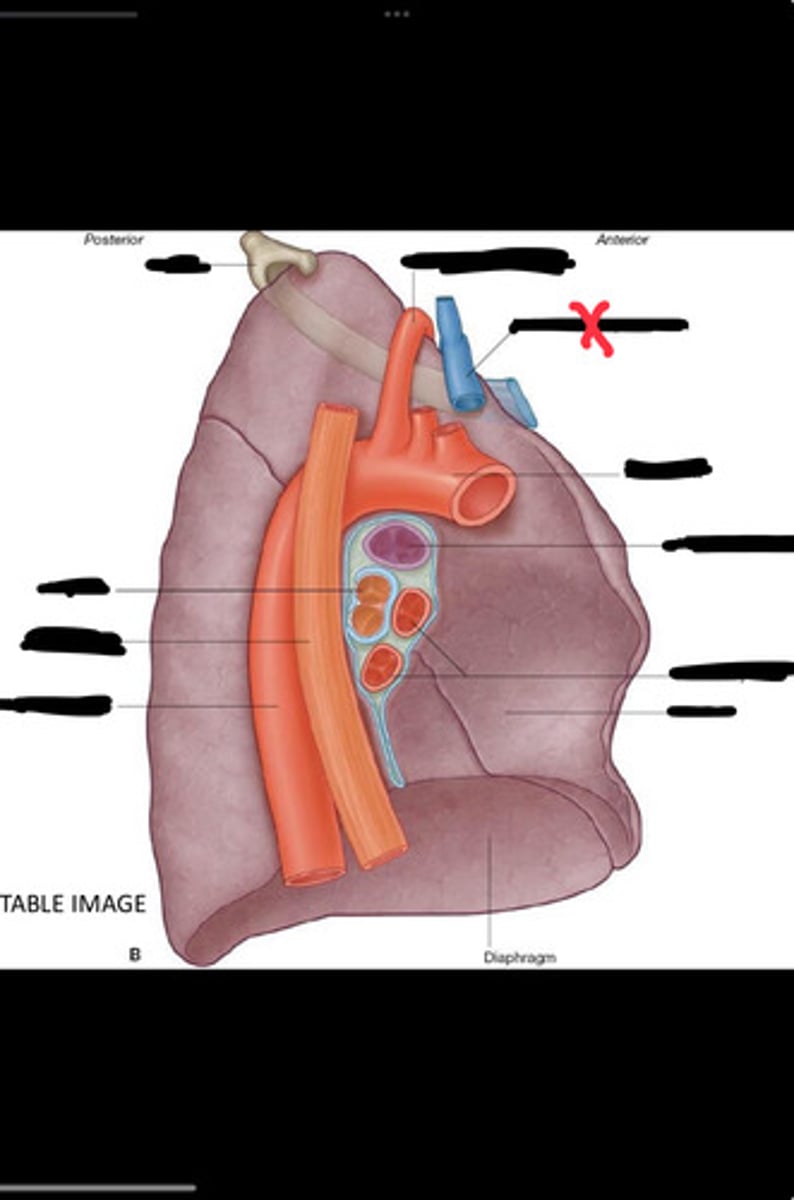

Diaphragm

Inferior vena cava

Superior vena cava

Subclavian vein

Right bracheocephalic vein

Subclavian artery

Esophagus

Bronchus

Rib 1

Left subclavian artery

Left brachiocephalic vein

Aortic arch

Pulmonary artery

Pulmonary vein

Heart

Left brachiocephalic vein

Azygos vein

Esophagus

Bronchus

Fibrous pericardium

Parietal layer of serous pericardium

Pericardial cavity

Visceral layer of serous pericardium

Junction between fibrous pericardium and adventitia

Heart

Thoracic aorta

Rib 1

Pulmonary artery

Bronchus to superior lobe